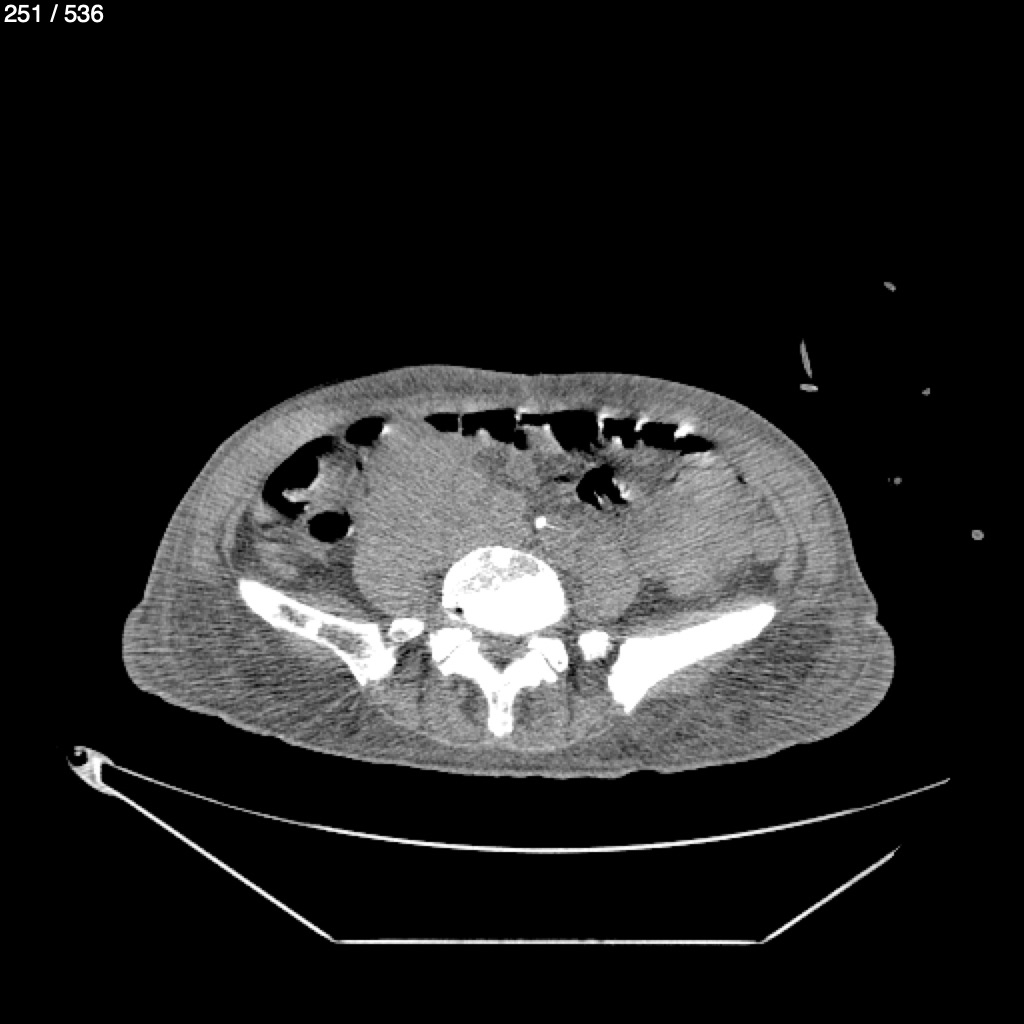

Angel Villalobos Palomeque 73 A - T.C Abdomen Simple